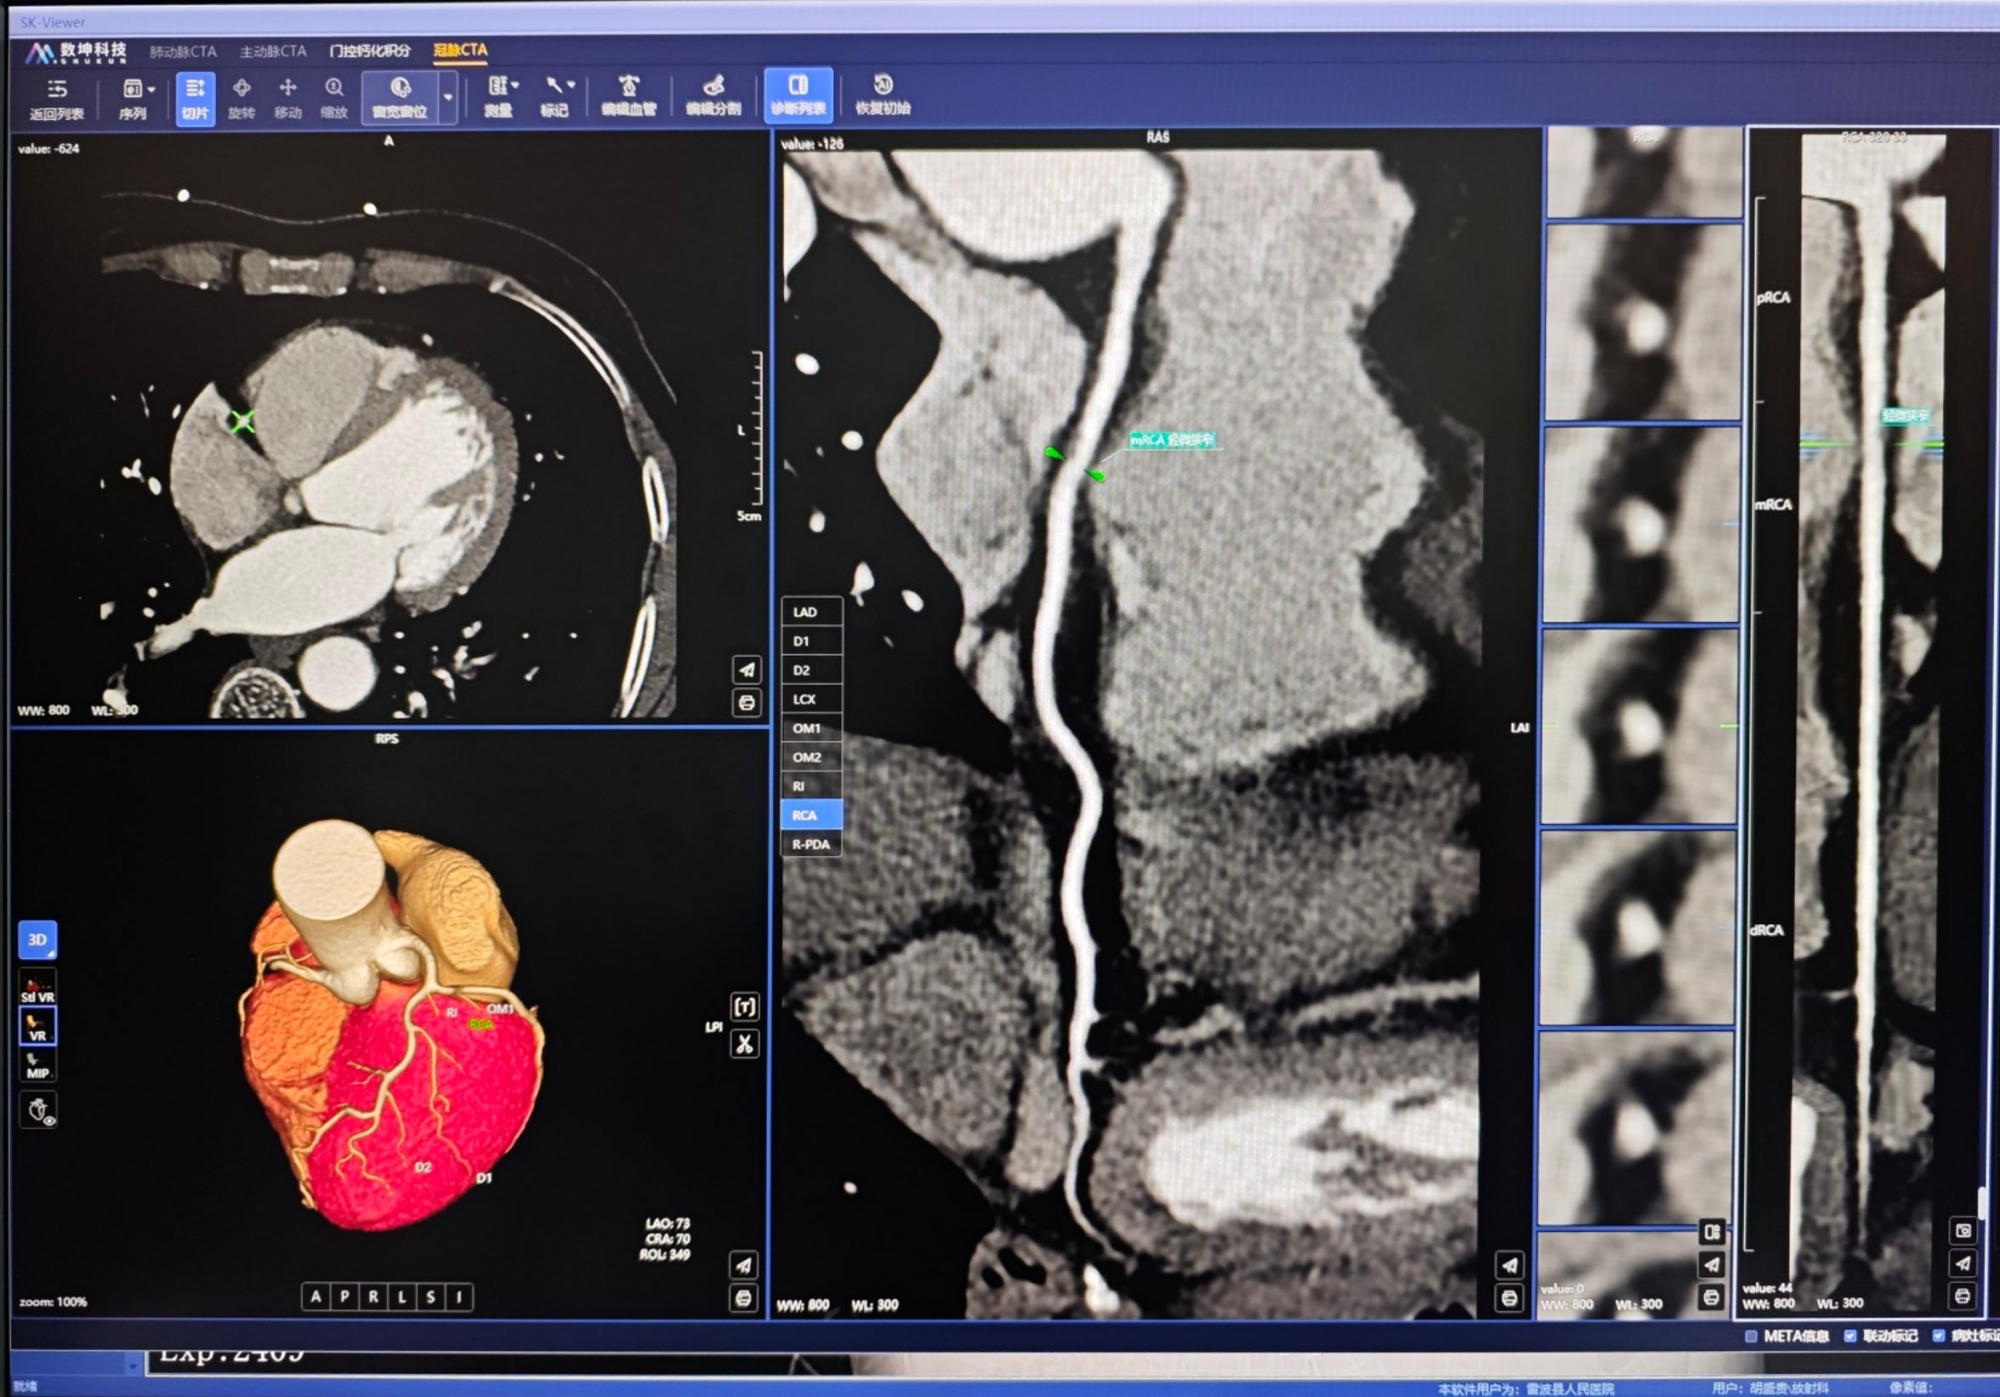

近日,在我院对口支援“传帮带”专家夏林的全程精准指导下,凉山州雷波县人民医院放射科团队成功完成该院有史以来图像质量最优的冠状动脉CTA(计算机断层扫描血管成像)检查。这项技术的全方位优化升级,标志着该院在心血管影像诊断领域取得关键性突破,区域心血管疾病诊疗能力自此迈上新台阶。

冠状动脉CTA作为高效、精准、无创的冠心病筛查核心技术,其成像质量直接影响临床诊疗决策。夏林与雷波县人民医院放射科严林军等医师深入研讨,通过医院PACS系统调取既往冠脉CTA图像,系统梳理出既往检查中存在的错层伪影、信噪比不足、造影剂浓度失衡、上腔静脉线束硬化伪影干扰等核心问题。检查前,他逐一排查患者身体状况,与家属充分沟通并完善知情同意书签署,筑牢检查安全规范防线。

在夏林的精准把控下,团队从心率调控、呼吸屏气训练、造影剂注射方案优化、静脉通道精准选择,到图像重建后处理等全流程细化打磨,最终获取超高清冠状动脉影像资料,为临床精准诊疗提供了坚实依据。该院放射科海来不者老师看到重建图像后激动表示:“这是联影60排螺旋CT(uCT710)装机以来,我们获得的最优质冠脉CTA图像!”

夏林介绍,县级医院虽受设备条件限制,无双源CT等高端配置,但只要在各扫描环节精益求精、严控干扰因素,国产60排CT完全可产出高质量冠脉CTA图像,切实为基层患者健康保驾护航。